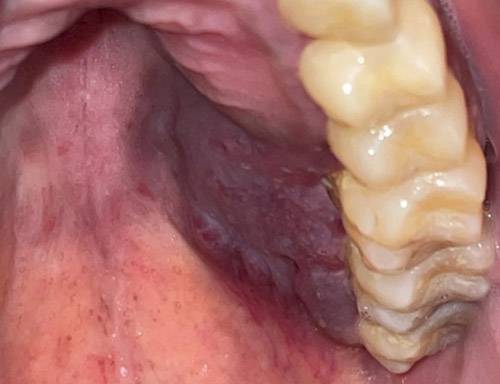

성(性)에 대한 인식이 갈수록 개방적으로 바뀌면서 파트너 수가 늘어나고, 성병 확산 위험도 높아지고 있다. 이때 주의해야 할 것이 에이즈로 이어지는 HIV(사람면역결핍바이러스) 감염인데, HIV 감염 증상이 입속에 나타날 수 있어 알아두는 게 좋다. HIV에 감염되면 '카포시육종'이라는 악성 종양이 생길 수 있는데, 일부는 입안 점막으로 증상이 발현된다. 프랑스 파리 파리시테대학교 피티에살페트리에르병원 치과 의료진이 HIV 감염으로 인해 입안 점막에 카포시육종이 나타난 사례 두 건을 보고했다.

피티에살페트리에르병원 치과 의료진은 "카포시육종은 1872년 처음 보고된 질병으로, HIV 감염 환자에게서 발생했을 때 이미 '에이즈 정의 질환'으로 간주된다"며 "남성과 성관계를 갖는 젊은 남성에게 가장 흔히 나타난다"고 했다. 이어 "붉은색이나 보라색 반점으로 나타나는 경우가 많다"고 했다. 단독으로 병변이 생기면 절제하는 외과적 수술, 방사선 치료 등으로 제거하고 광범위하게 퍼졌을 때는 항암치료 등을 고려한다. 에이즈 상태로 진행됐을 경우 항바이러스 치료제를 써서 면역력이 떨어지지 않도록 유지시킨다.